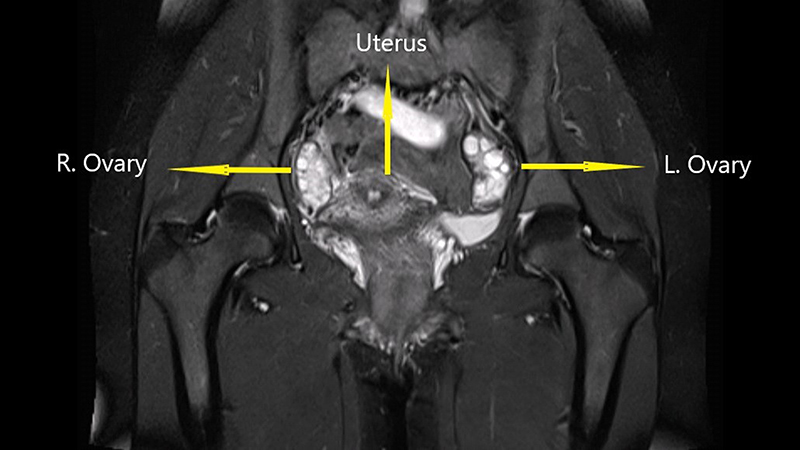

Recenti linee guida raccomandano una diagnosi clinica basata sui sintomi, sull'esame fisico e sull'imaging. La ricerca di prima linea è l'ecografia, un test economico e facilmente accessibile; l'ecografia transvaginale di base, eseguita nella maggior parte delle unità ecografiche, può essere utilizzata per diagnosticare gli endometriomi con elevata precisione e può anche escludere altre patologie pelviche. In alternativa può essere utilizzata la risonanza magnetica, che ha una sensibilità e specificità simili all'ecografia transvaginale (Fig. 3).

Figura 3. Risonanza magnetica di apparato genitale femminile.